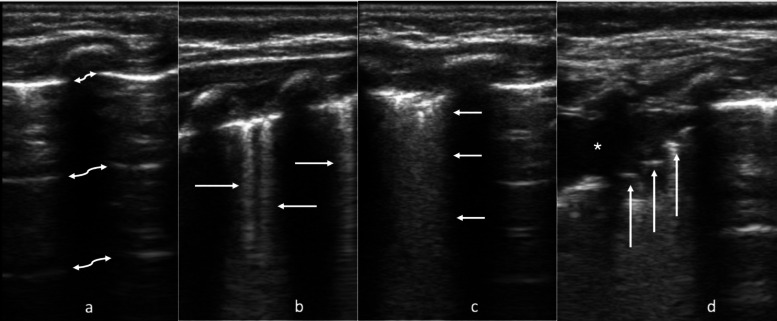

Methods: Infants ≤ 12 months diagnosed with AB in the emergency department were enrolled. Two LUS techniques were performed sequentially: a 12-segment "lawnmower" approach and a posterior paravertebral "waterfall" technique. LUS were scored (0-36 for lawnmower; 0-6 for waterfall). Respiratory support (RS) was categorized into three levels: no RS (room air), low RS (wall O2 or heated high flow nasal cannula < 1L/kg), and high RS (heated high flow nasal cannula ≥ 1L/kg or positive pressure). Clinical data, including RS at 12 and 24 h, maximum RS, disposition, and length of stay, were extracted via chart review and compared to mean LUS scores for each technique. Calculated areas under the curve (AUC) were compared using the Youden Index (J).